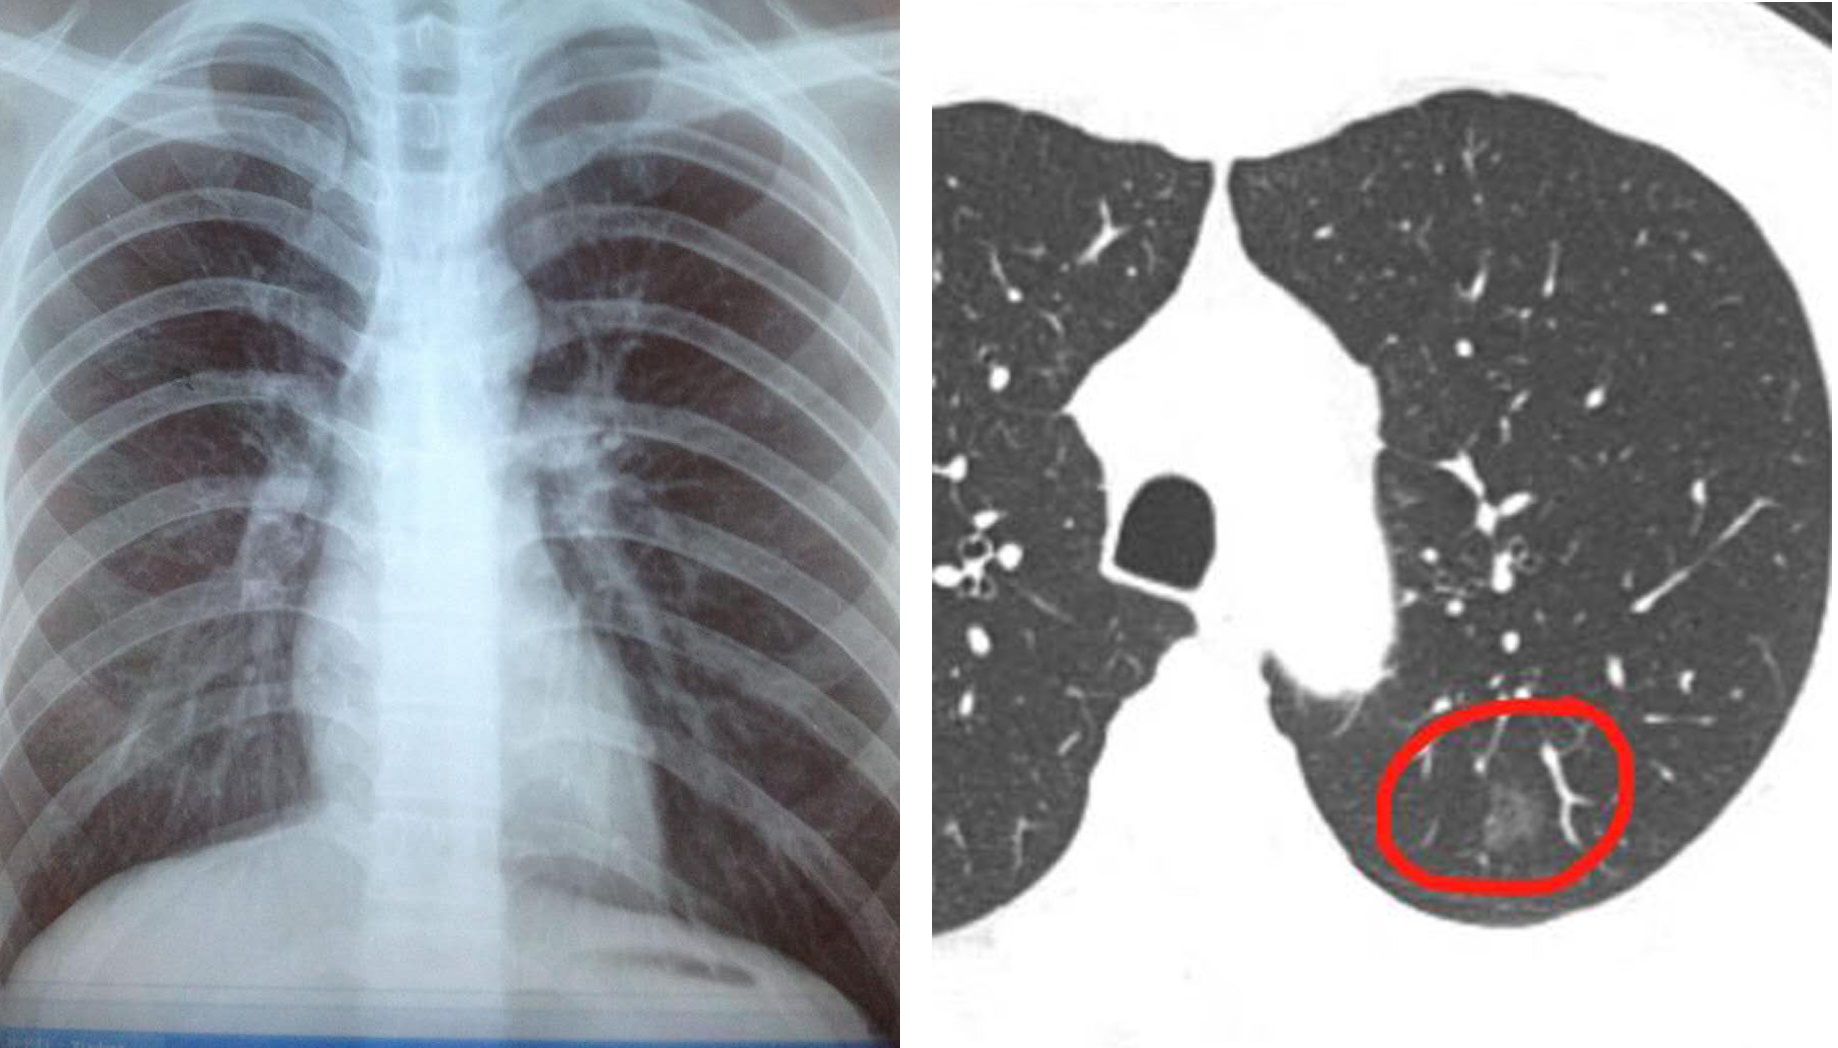

胸片是通过机器发出X射线穿透人体之后被探测器捕捉,并得到了一副透视胸部的平面图像。而CT是多层螺旋扫描,把脏器的分层扫描得出多副图像(分多少层,就能得到多少副图像)。CT扫描的好处在于不仅可以分层检查脏器,还可以通过不同的角度旋转三维重建观察病灶特征。而拍片是平面图,达不到CT的三维效果及病灶的准确位置。例如下图胸片以及胸部CT,其中胸片中专门画出来很多横线,代表CT切的每个层面。

同理胸片,一个平面的扫描透视片中,不仅涵盖肺组织,还包含肋骨等。与肋骨前后重叠的肺组织中的结节灶非常容易被漏诊。此外,胸片容易漏诊心脏影后面的病灶:上面胸片CT对比图中,左边胸片中间梨形白色的影子为心脏影,他有一部分与肺前后重叠。也就是说一个平面透视时,有一部分肺组织是被心脏挡住的。因此心影后面肺部病灶胸片很容易漏诊,而CT就不用担心这个问题。其他还有肺门部位因为血管非常丰富,所以肺部部位的阴影往往因为与血管混杂一起而漏诊。

再次回归现实中的一例早期肺癌患者,这名患者前面单位体检拍胸片未见异常,随后因其他原因行胸部CT检查,无意中发现一枚磨玻璃结节,最后手术结果显示为早期肺癌。如下图:左侧胸片中完全看不到的肺部结节,而右图胸部CT的其中一个层面能看到胸膜下9mm的肺部磨玻璃结节灶。